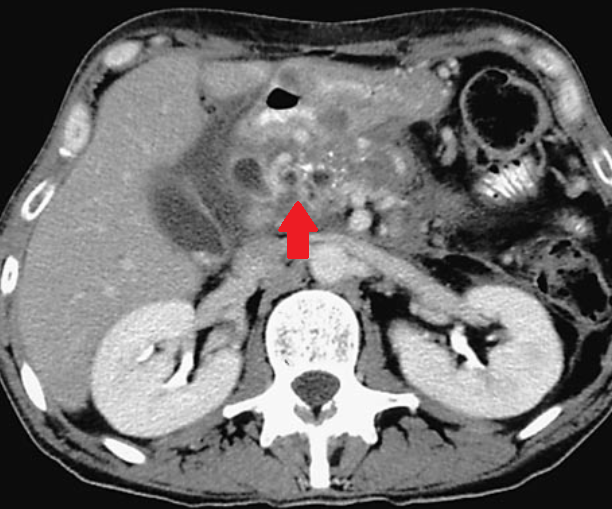

Polycystic liver disease. Red arrow. Infected hepatic cyst (Courtesy Dr. V. Penopoulos)